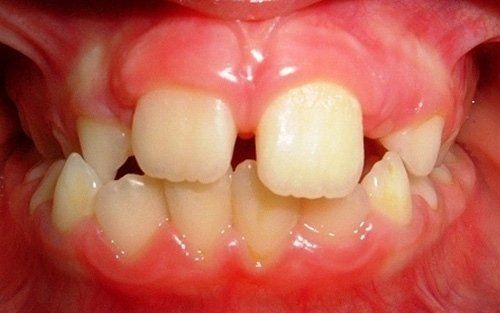

La "doppia fila" di denti: preoccupazione per i genitori

Una grande preoccupazione per i genitori è rappresentata dalla presenza contemporanea dei denti permanenti e dei denti da latte (che non cadono).Questa condizione non è affatto pericolosa per i denti permanenti, che prima o poi andranno a posizionarsi nella loro sede definitiva, dando l'ultima spinta ai dentini da latte, che cadranno definitivamente. Tranne rare accezioni, non vi è alcuna necessità di traumatizzare il bambino anticipando questo processo naturale con fastidiose estrazioni dentali.

Ecco un classico esempio di contemporaneità di denti da latte e denti permanenti. Questa situazione preoccupa sempre molto i genitori.